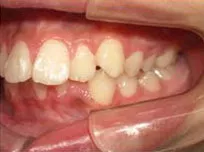

症例1

| 治療期間 | 11ヶ月(2021年6月〜2022年5月) |

| 費用 | 495,000円(税込) |

| リスクや副作用 | 成長期が終わった18歳以降に、2期矯正が必要になることがある |